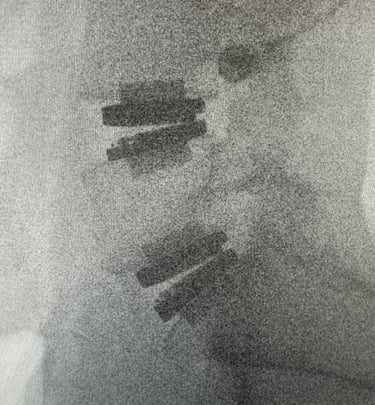

Snapshots of precision in lumbar spine imaging

Precision Imaging

Delivering clear, detailed spinal exposures.